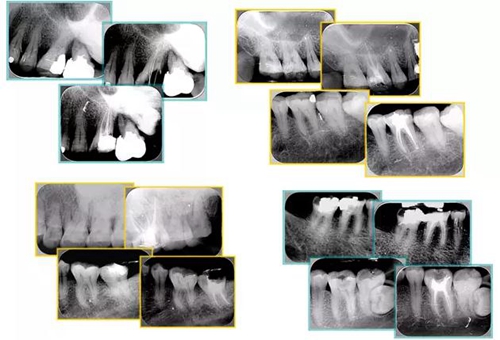

6. 術(shù)后 X 線片

術(shù)后 X 線片用來(lái)評(píng)定根管充填 長(zhǎng)度、致密度(管壁清晰、側(cè)枝)等指標(biāo)。

15.jpg

左圖為根管充填術(shù)后 X 線片。圖中可見(jiàn),根管充填較好。右下圖有白色小點(diǎn),為側(cè)方加壓導(dǎo)致糊劑擠出所致,表明根管充填比較致密。

致密、恰到好處的充填可去除干凈根管里感染灶,機(jī)體逐漸恢復(fù)。

16.jpg

多根牙時(shí)候需進(jìn)行偏移投照,正位投照無(wú)法說(shuō)明具體哪根牙根管充填效果。